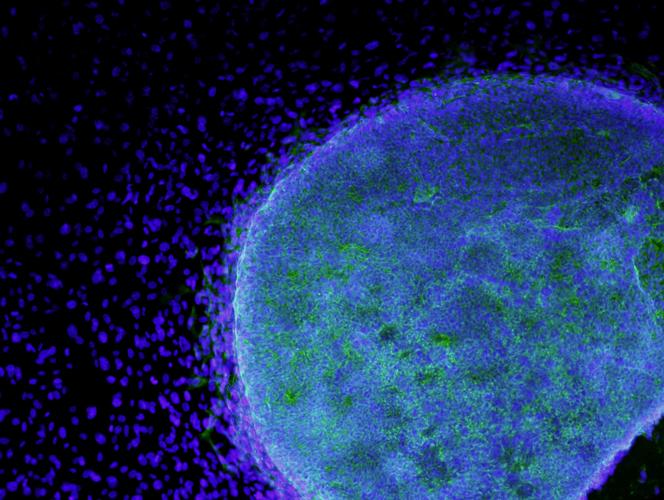

Position de principeModification génétique d’un embryon humain en Chine : bienvenue dans ce monde où l’Occident a perdu le monopole de la science de pointe (et des choix éthiques...)

Mi-avril, un groupe de scientifiques chinois a publié une étude dans la revue Protein and Cells dans laquelle ils décrivent leurs recherches visant à modifier génétiquement des embryons humains. Quelques semaines auparavant, les dirigeants d'une entreprise américaine avaient appelé à un moratoire contre la manipulation des cellules humaines.